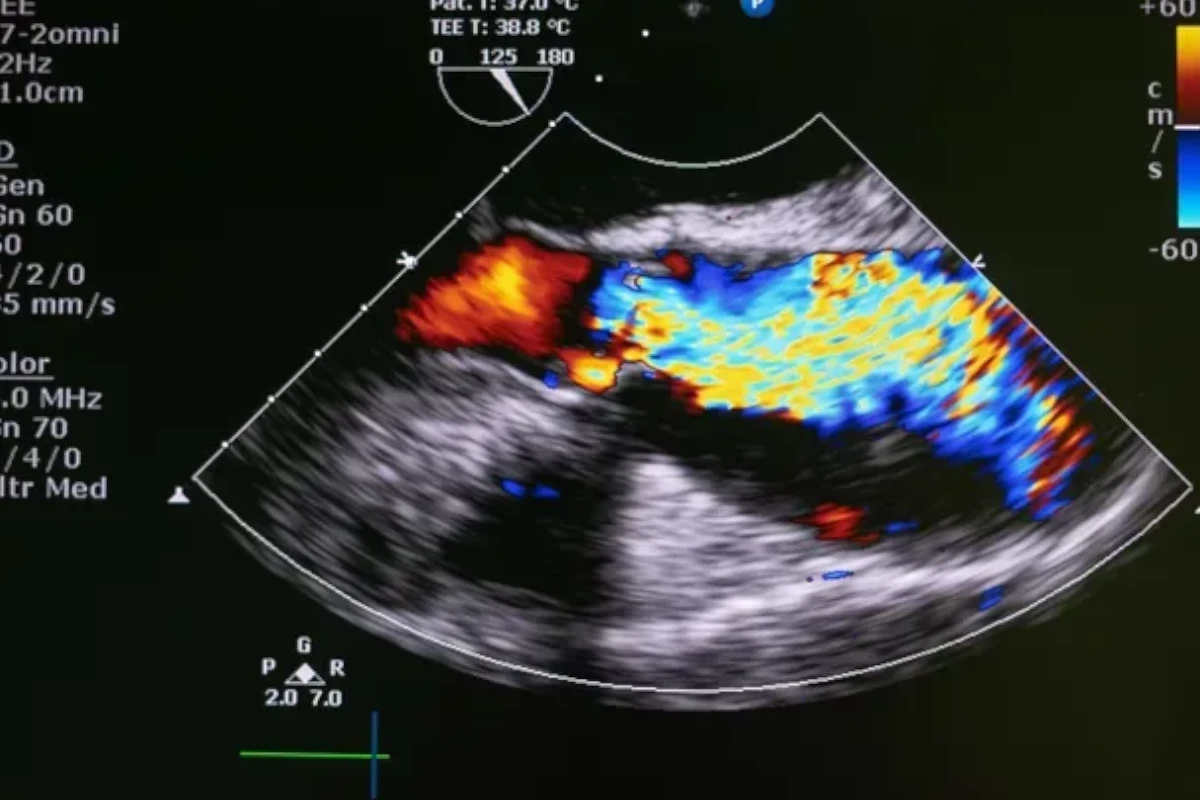

Echocardiogram

Our specialists assess and treat valve disorders to restore normal heart rhythm and ensure efficient blood flow throughout the cardiovascular system.

We perform MitraClip therapy to treat mitral valve regurgitation, improving heart efficiency and reducing symptoms without the need for surgery.